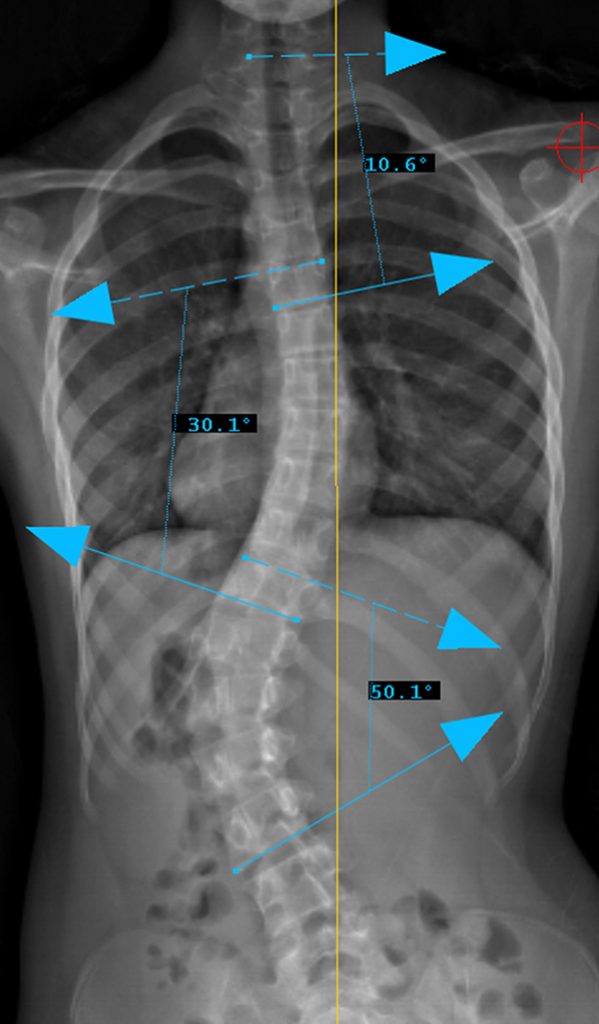

Curve Type 5

Lumbar curve major, other curves non-structural.

Lumbar modifier C

CSVL does not touch apex of lumbar curve

(apex - L1/2 disc)

Therefore, Classification is Type 5CN

Lenke Type V describes a major curve in the thoracolumbar/lumbar region. The apex of the greatest coronal plane deformity is between T12 and L4. The main thoracic curve is non-structural with a side-bending Cobb of less than 25 degrees and a T10-L2 kyphosis of less than 20 degrees. All of these curves have a “C” lumbar spine modifier. The three sagittal modifiers are still applicable. These curves may be treated with either an anterior or posterior spinal fusion. The fusion levels are often the upper and lower end-vertebrae of the coronal plane deformity. For successful selective fusion of the thoracolumbar/lumbar spine the Cobb angle, apical vertebral translation, and apical vertebral rotation ratios (ThL/L:MT) should be greater than 1.25. In addition the MT curve should be flexible without evidence of thoracolumbar junctional kyphosis (T10-L2 > 20 degrees).

Preop: 5CN Examples

Preop PA View